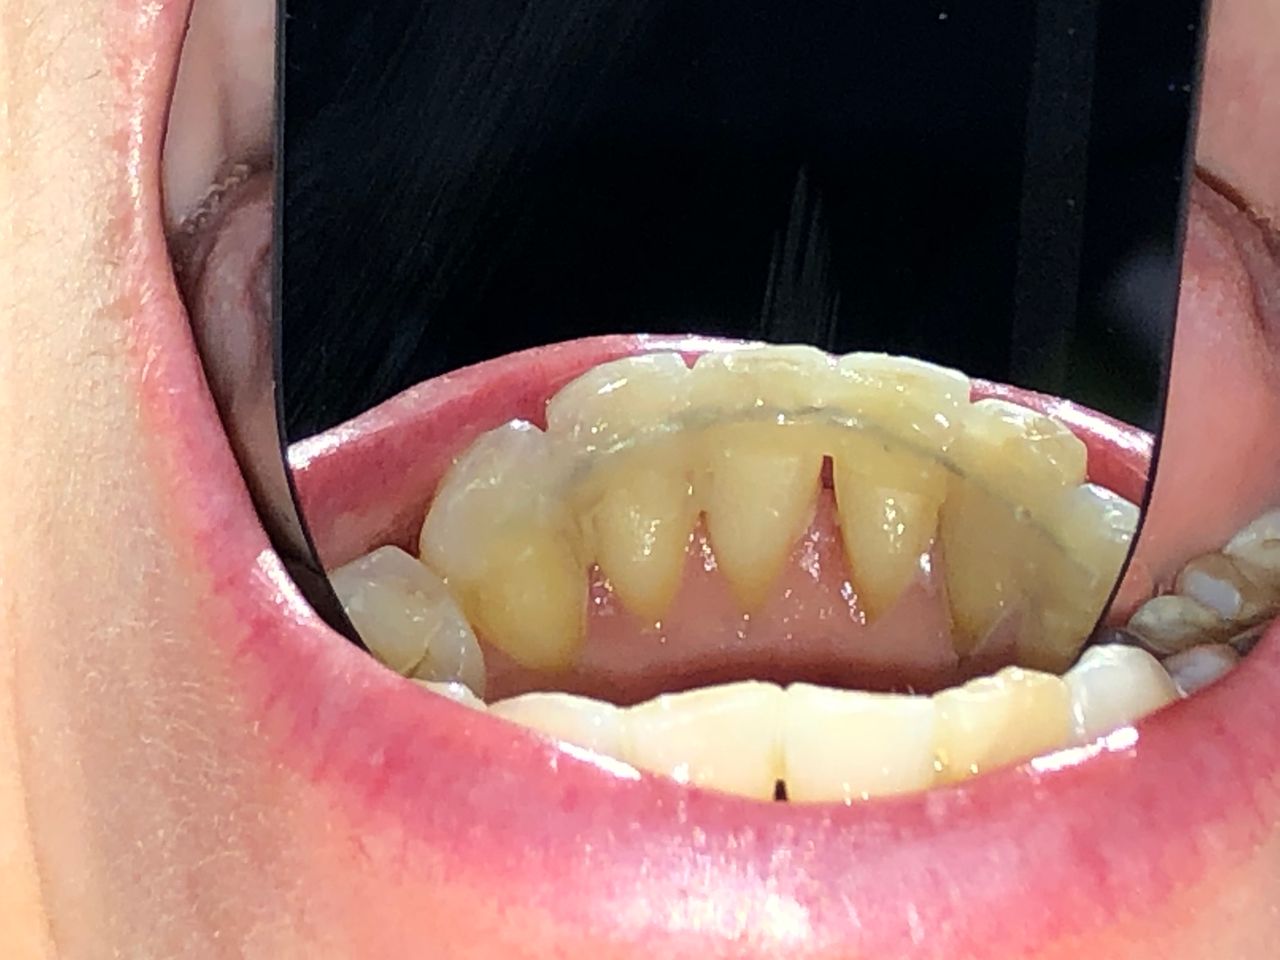

Foto e video